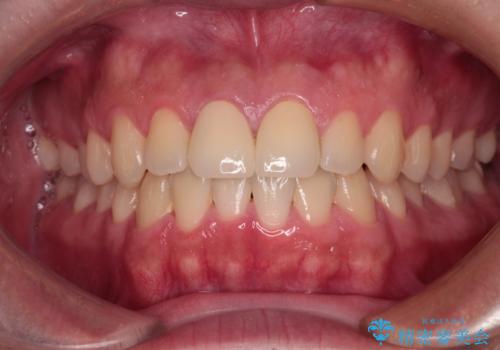

無菌的環境下にて歯の状態を調べ、最終的にオールセラミッククラウンにて補綴治療を行うこととしました。

幸いにも神経組織に影響はなく、健全な状態で治療を終えることができました。

歯肉の腫脹が目立っていたため、衛生指導も並行して行い、引き締まった歯肉になりました。

外傷歯は、将来的に歯根吸収を起こす可能性があるため、定期的なレントゲン撮影により経過観察が必要となります。